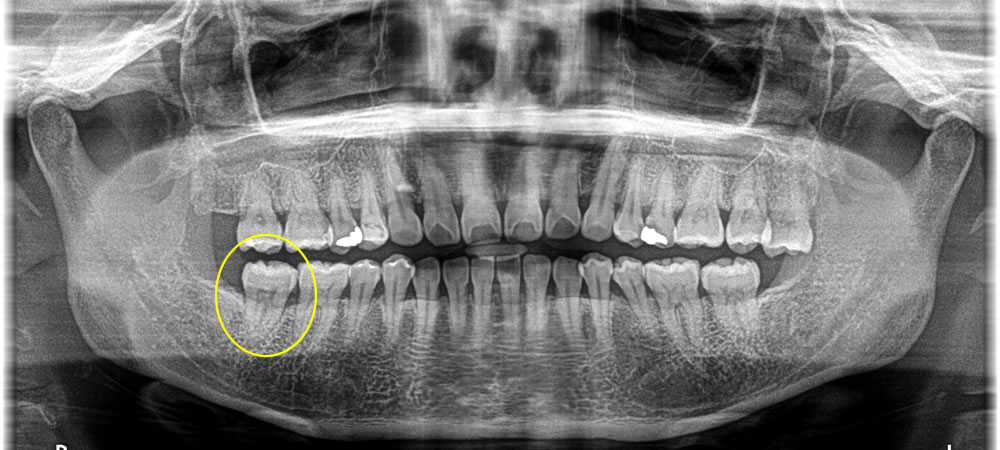

歯根破折した歯を抜歯してインプラントで治療した症例

こちらは、右下一番奥の歯が噛むと痛いとのことで来院された患者さまです。

レントゲン、口腔内検査の結果、歯根に破折線がみられたため、患者様と相談し、破折した歯を抜いてインプラント治療を行う計画を立てました。